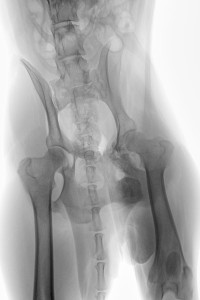

Die Spinone ltaliano Hündin „Ajenna“ gerufen Jenna, geb. April 2013, wk, ist am 06. Oktober 2015 auf der unweit entfernten Bundesstraße vor ein Auto gelaufen und wurde angefahren. Durch den seitlichen Aufprall auf die linke Körperseite kam es zu einem stumpfen Trauma im Brustbereich mit Lungenrissen und das Becken wurde mehrfach frakturiert. Wie auf den RÖ-Bildern zu sehen, war das Schambein verschoben, das Becken gebrochen, aber die größte Sorge machte uns die Fraktur im caudalen Bereich des Acetabulums. Da der Hund das Hinterbein mäßig belasten konnte und die Band- und Kapselstrukturen des Hüftgelenkes scheinbar intakt und nicht gerissen waren (der Femurkopf war nicht luxiert), sah der hinzugezogene Orthopäde von einer sofortigen OP ab und wollte zunächst den Heilungsverlauf beobachten.

Auf der Kontroll-RÖ-Aufnahme vom 19. Okt. konnte noch keine Kallusbildung festgestellt werden.